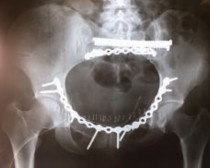

Окончательная фиксация переломов таза выполнялась нашим пациентам в отсроченном порядке, на 10-14 сут, после устойчивой адаптации организма к новым условиям, в двух случаях оперативное вмешательство выполнено на вторые сутки после травмы [5, 6]. Всем пациентам выполнена открытая репозиция, фиксация тазового кольца тазовыми пластинами А.О. фирмы Synthez, 32 пациентам выполнена инверсия аппарата внешней фиксации на погружные конструкции [6]. В после операционном периоде пациенты получали антикоагулянтную, антибактериальную терапию, инфузионную терапию. ЛФК под контролем инструктора начинали с 3 суток после операции [7].

Клиническое наблюдение 1: Пациент Т., 25 лет, травма получена в результате ДТП (мотоциклист). Диагноз при поступлении: Политравма. ЗЧМТ. Сотрясение головного мозга (при поступлении сознание ясное). Закрытая травма грудной клетки. Множественный, осложненный левосторонним гемопневматораксом, перелом ребер, с 3 по 11 ребро. Закрытый вертикально нестабильный перелом таза, С3 по классификации А.О. Тяжесть состояния по шкале ISS – 35 баллов. При поступлении гемоглобин 78 г/л, гематокрит 25%. Учитывая тяжесть состояния, пациент после поступления переведен в ОРИТ, где выполнено дренирование левой плевральной полости, выполнена стабилизация перелома таза АНФ, перелито 2 дозы эритроцитарной массы. Через 5 дней после контрольной рентгенографии грудной клетки дренаж удален. На 14 сутки выполнена стабилизация переднего и заднего полукольца таза пластиной А.О., канюлированными винтами. Через три дня после операции пациент переведен в профильное отделение, где продолжена симптоматическая, антибактериальная, инфузионная, антикоагулянтная терапия. На 30 сутки пациент выписан из стационара в удовлетворительном состоянии.

Клиническое наблюдение 2: Пациент М., 54 года, травма получена при падении, во время катании на лыжах, доставлен в день травмы в стационар бригадой МЧС в противошоковом костюме. Диагноз при поступлении: Политравма. ЗЧМТ. Сотрясение головного мозга. Изолированный нестабильный перелом костей таза В3 по классификации А.О., состояние пациента по шкале ISS - 20 баллов. Учитывая характер травмы, отсутствие других повреждений, решено оперировать пациента на следующие сутки после травмы, а предоперационную подготовку продолжить в ОРИТ. При поступлении гемоглобин 100 г/л, гематокрит 27%. На следующий день пациенту была выполнена открытая стабилизация переднего полукольца пластиной А.О., стабилизация заднего полукольца винтами А.О. Ранний послеоперационный период протекал без особенностей, проводилась симптоматическая, антибактериальная, инфузионная, антикоагулянтная терапия. С третьего дня от момента операции начата ЛФК. Пациент выписан в удовлетворительном состоянии из стационара на 17 сутки от момента травмы. Через год рентгенологический и функциональный результат хороший.